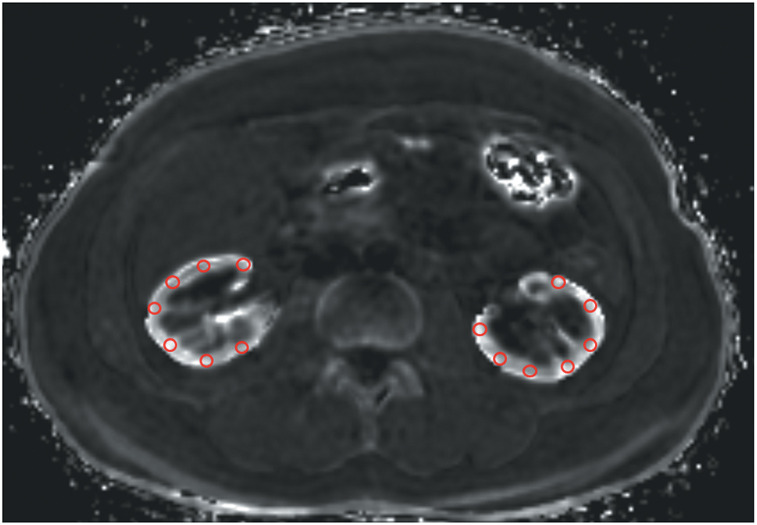

Purpose: The kidney iron deposition can cause kidney damage and renal insufficiency in paroxysmal nocturnal hemoglobinuria (PNH) patients. Assessment of iron deposition in the kidney is essential for the early diagnosis of renal damage in PNH patients. The purpose of this study was to evaluate kidney R2* (T2* reciprocals) values in PNH patients using the iterative decomposition of water and fat with echo asymmetry and least-squares estimation (IDEAL-IQ).

Methods: Two radiologists measured the R2* values of the renal cortex in 14 PNH patients and 13 healthy volunteers using IDEAL-IQ. Lactate dehydrogenase (LDH), a reliable marker of intravascular hemolysis, was also measured in all participants.

Results: The kidney R2* values were significantly higher in PNH patients compared with those in healthy volunteers (P < 0.001). High inter-operator reproducibility of the measurements was also acquired using IDEAL-IQ. LDH levels were also significantly higher in PNH patients compared with those in healthy volunteers (P < 0.001). Kidney R2* values strongly correlated with LDH levels in PNH patients.

Conclusion: IDEAL-IQ has a possibility of becoming a useful method for the noninvasive evaluation of renal iron overload in PNH patients.